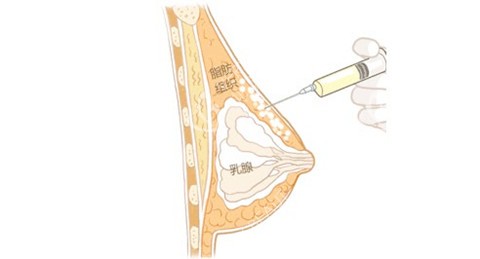

关于按摩,术后早期应避免,但两年后可适当进行轻柔按摩,促进局部血循环。若发现硬结,应避免用力按压,并***医生。

定期自我检查不容忽视。每月应检查乳房是否有新增硬结、疼痛或形态变化。自体脂肪隆胸一般不影响乳腺疾病筛查,但仍建议定期进行乳腺超声检查,以便***评估乳腺健康状况。

脂肪结节或钙化:较小的结节通常无需处理,若明显增大或伴有疼痛应及时就医。超声检查可区分一般结节和需处理的异常钙化。